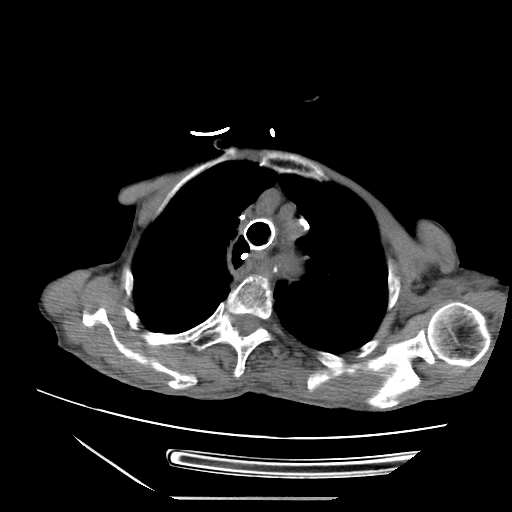

术前食管气管瘘

急诊医生第一时间为朱阿姨安排了全面检查,结果让人揪心:胸部CT提示两肺炎症、心包积液,结合其食管癌术后病史,高度怀疑“食管气管瘘”!血常规检查显示,她的白细胞计数12.95×10⁹/L(正常参考值3.5-9.5×10⁹/L),中性粒细胞百分数94.63%(正常参考值40-75%),降钙素原1.70ng/mL(正常参考值<0.05ng/mL),各项指标均指向严重感染。更危急的是,血气分析显示她的氧分压仅71.0mmHg,已出现I型呼吸衰竭。

首先是吻合口的长期隐患。食管吻合口是食管癌术后食管与其他消化道器官连接的“接口”,本身就是薄弱环节。朱阿姨今年5月就查出吻合口多发溃疡,长期的溃疡不断侵蚀周围组织,逐渐破坏食管壁,而食管与气管距离极近,最终溃疡穿透食管壁,与气管“打通”形成瘘口。

其次,术后纵隔结构改变增加了诊治难度。食管癌手术会改变胸腔内正常的解剖结构,像朱阿姨这样的食道癌根治术后“胸腔胃”,纵隔内组织还可能出现粘连,导致瘘口位置隐蔽,常规检查难以精准定位。